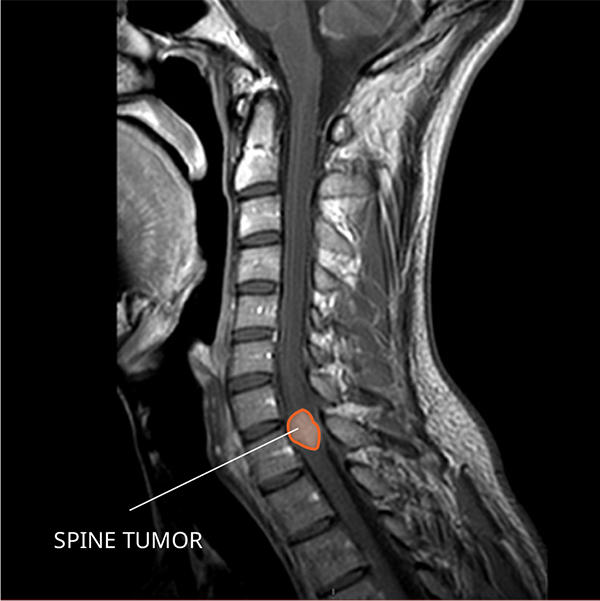

What Do Ependymomas Look like on an MRI?

Ependymomas usually appear as one or more well-defined masses that often brighten with contrast on a magnetic resonance imaging (MRI) scan.